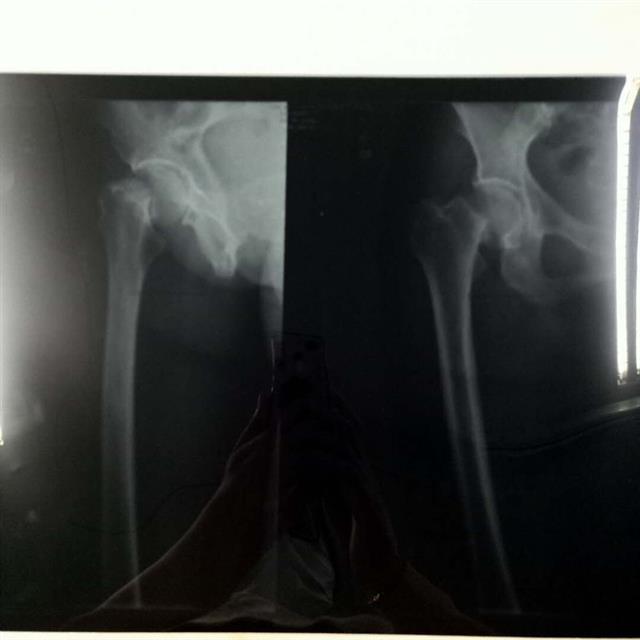

今天上午,楚天都市报记者来到湖北省人民医院骨科,邓兰芝躺在病床上,活动不便。医院X线检查报告显示,其左侧股骨颈骨折。周师傅说,事后,公司派人来医院看望过,但没有垫付医药费,提出让家属先垫付,事后再报销。因手术费初步确定要8万元左右,家里一下子拿不出这么多钱,希望物业公司直接垫付。